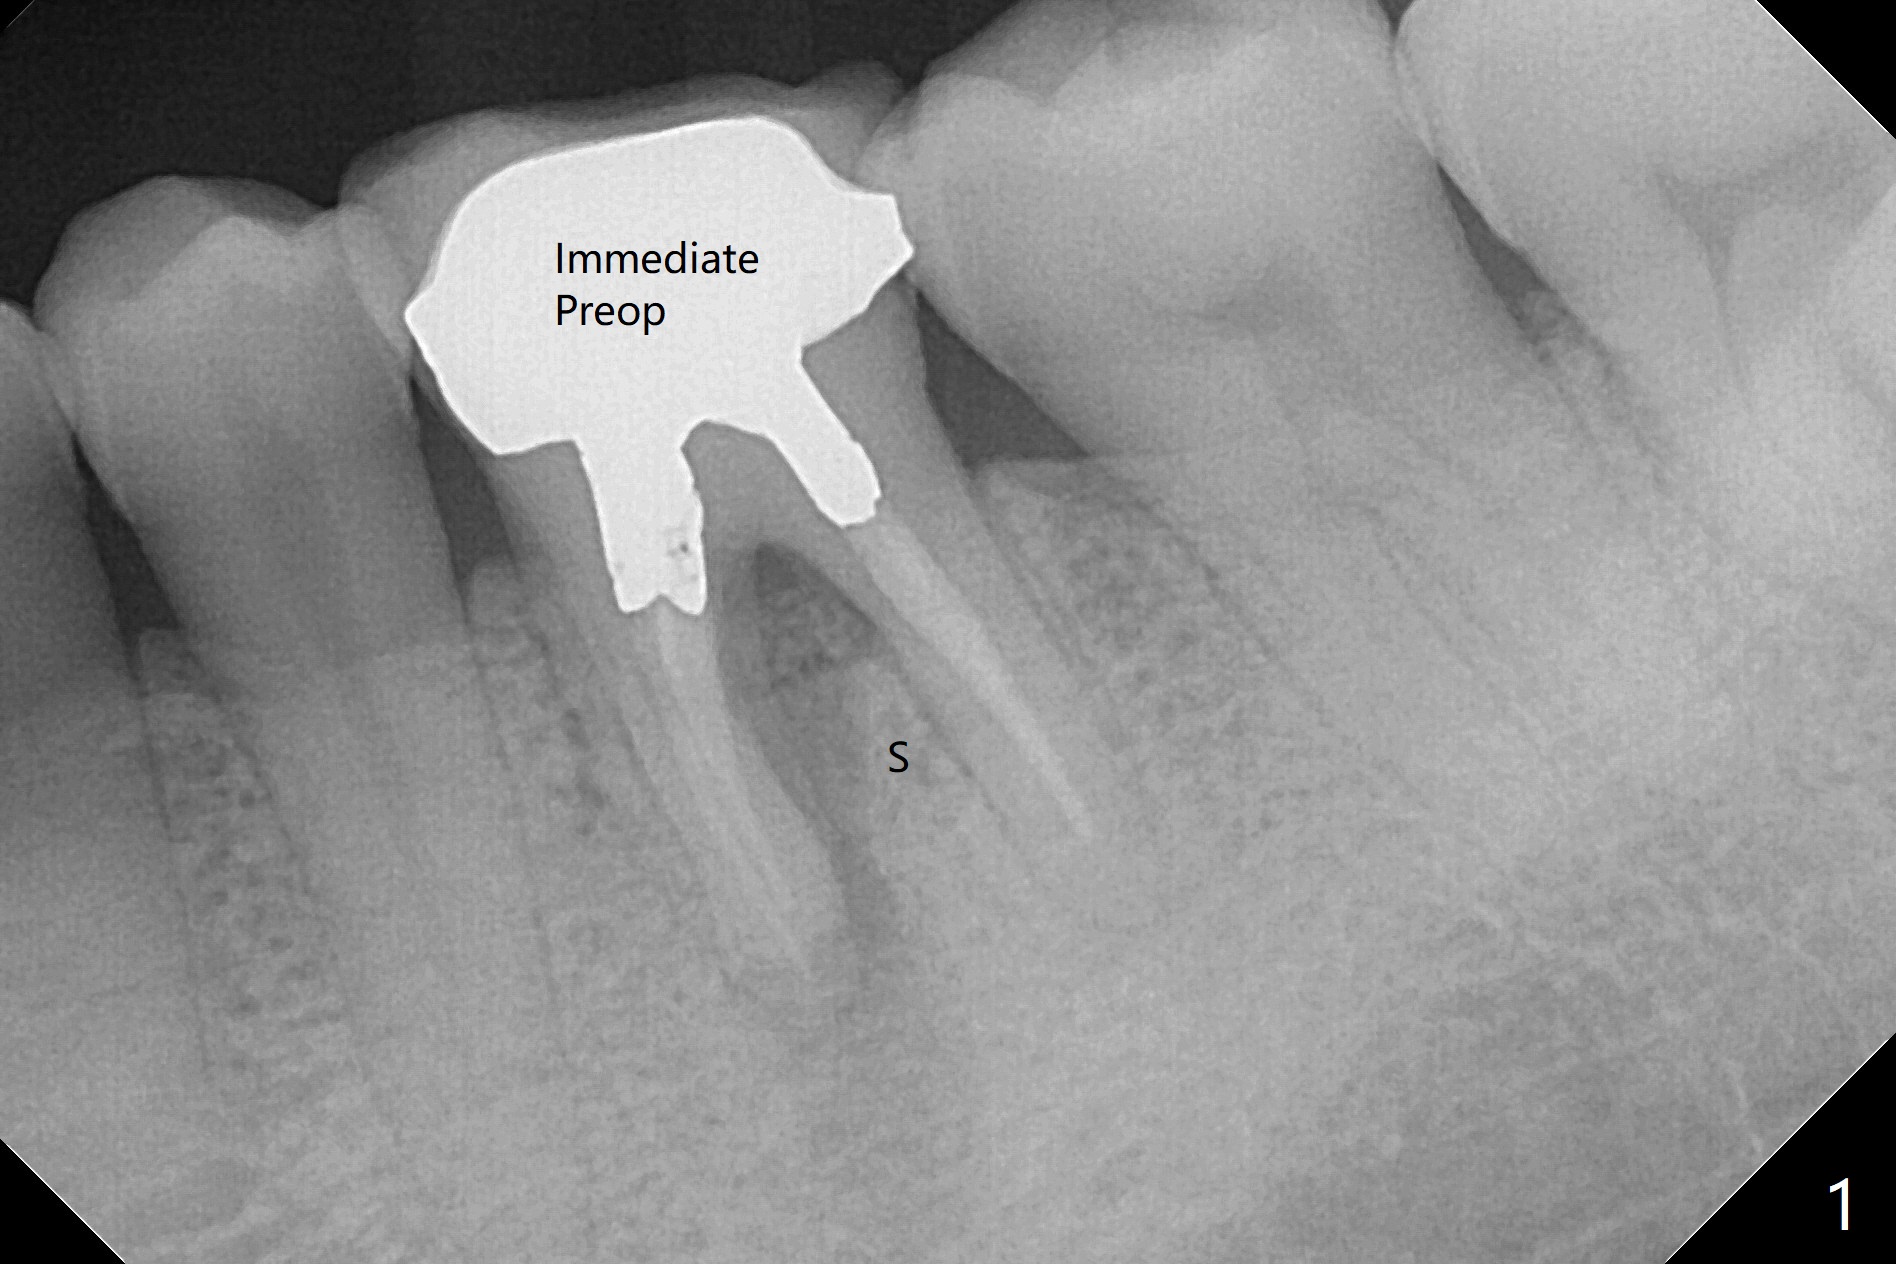

When the patient returns for #15 comp, the bone resorption and swelling at #19 are worse than those 3 years ago (Fig.1,2). After debridement, the mesial socket is large, while the septum is thin, irregular and with undercut (Fig.3). It seems difficult to obtain primary stability for an immediate implant. Vanilla bone and cortical bone hydrated with GEM21 S are placed for socket preservation (Fig.4,5), followed by 12x12 mm BioXclude and 4/0 PGA. In fact the bone height is limited for an immediate implant (Fig.6 (5x10 mm)). There is not enough bone in the septum for primary stability (Fig.7 (cross section of 3D image; L: lingual)). The socket heals 16 days postop (Fig.8). It appears that the granulation tissue is covered by a thin layer of granulation tissue (Fig.9 *), while the membrane remains in place (M). In fact the bone graft remains in the soft tissue zone as well as the hard tissue one (Fig.10). In spite of no apparent loss of bone graft (Fig.4,10), the graft seems to shrink in height 3.5 months postop (Fig.11), while the crest decreases (compare Fig.1 and 11). The keratinized gingiva is wide, but the alveolus reduces in width (Fig.12). The buccal crestal bone is lost 3.5 months postop (Fig.13).